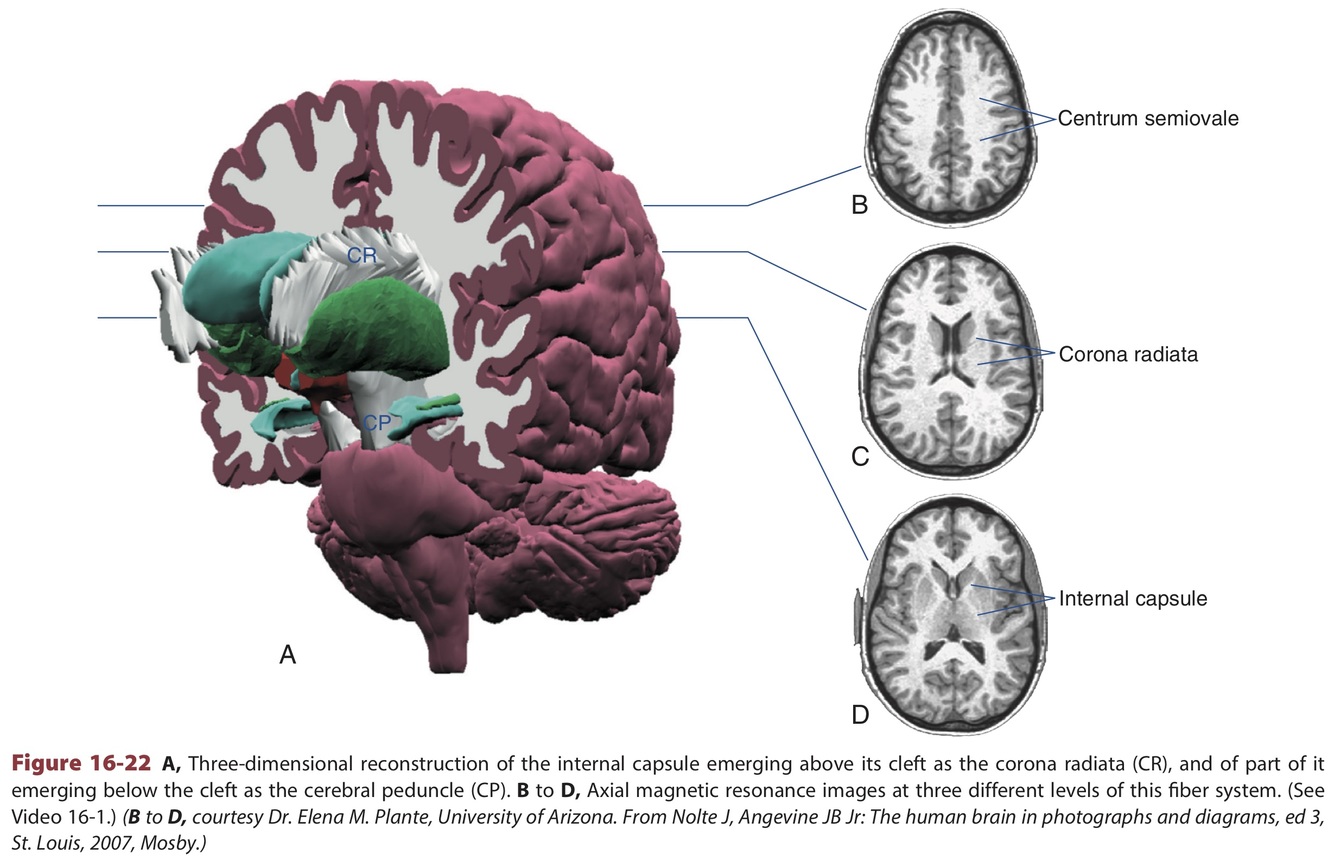

All fibers pass through centrum semiovale.

Fibers connecting cortical and subcortical regions also pass through corona radiata and internal capsule.